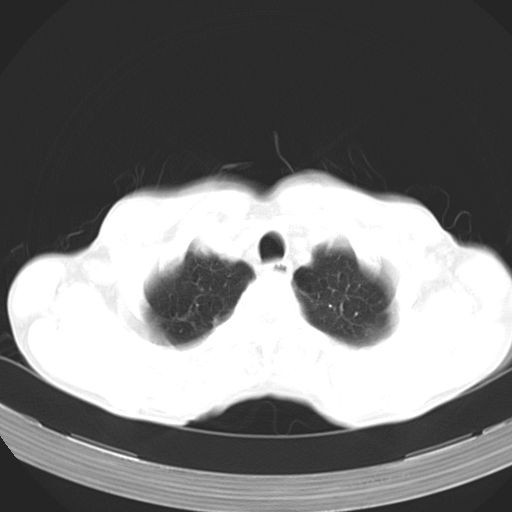

以下是引用苯小孩在2007-5-24 12:47:00的发言:[br]右侧肺门处不均匀密度软组织块影,远端肺组织见斑片模糊影,纵隔内淋巴结明显肿大,边界不清.<纵隔窗第12层面支气管内似见软组织结节>[br]考虑:1、右侧中央性肺癌并阻塞性肺炎并纵隔淋巴结转移可能性大.建议强化或纤支镜进一步检查.[br]2、隆突下淋巴结肿大/食道病变?请做鉴别检查.

以下是引用jw-830在2007-5-24 15:24:00的发言:[br][br] [br] 考虑右肺中央型肺癌并阻塞性炎症,右肺门及纵隔淋巴结转移。 [br] [br][br]